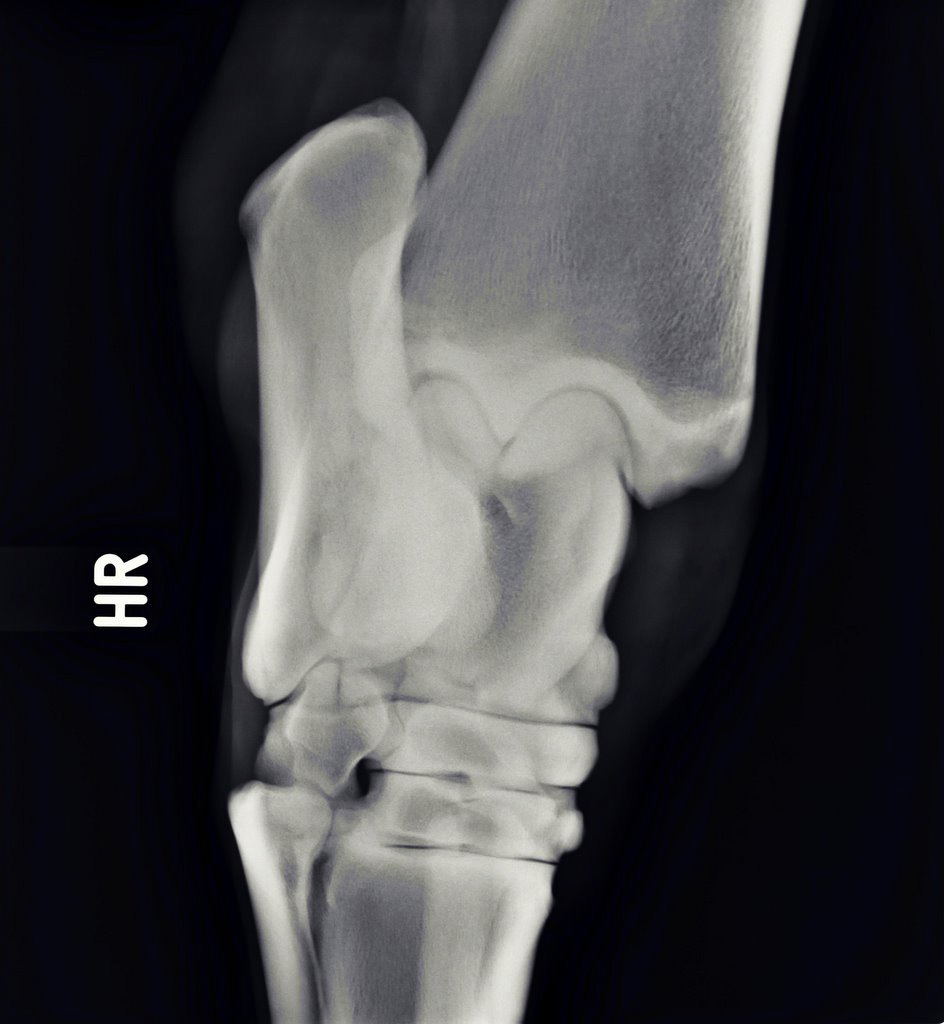

Illustrative Mindeststandardaufnahmen zur Beurteilung nach dem Röntgenleitfaden: